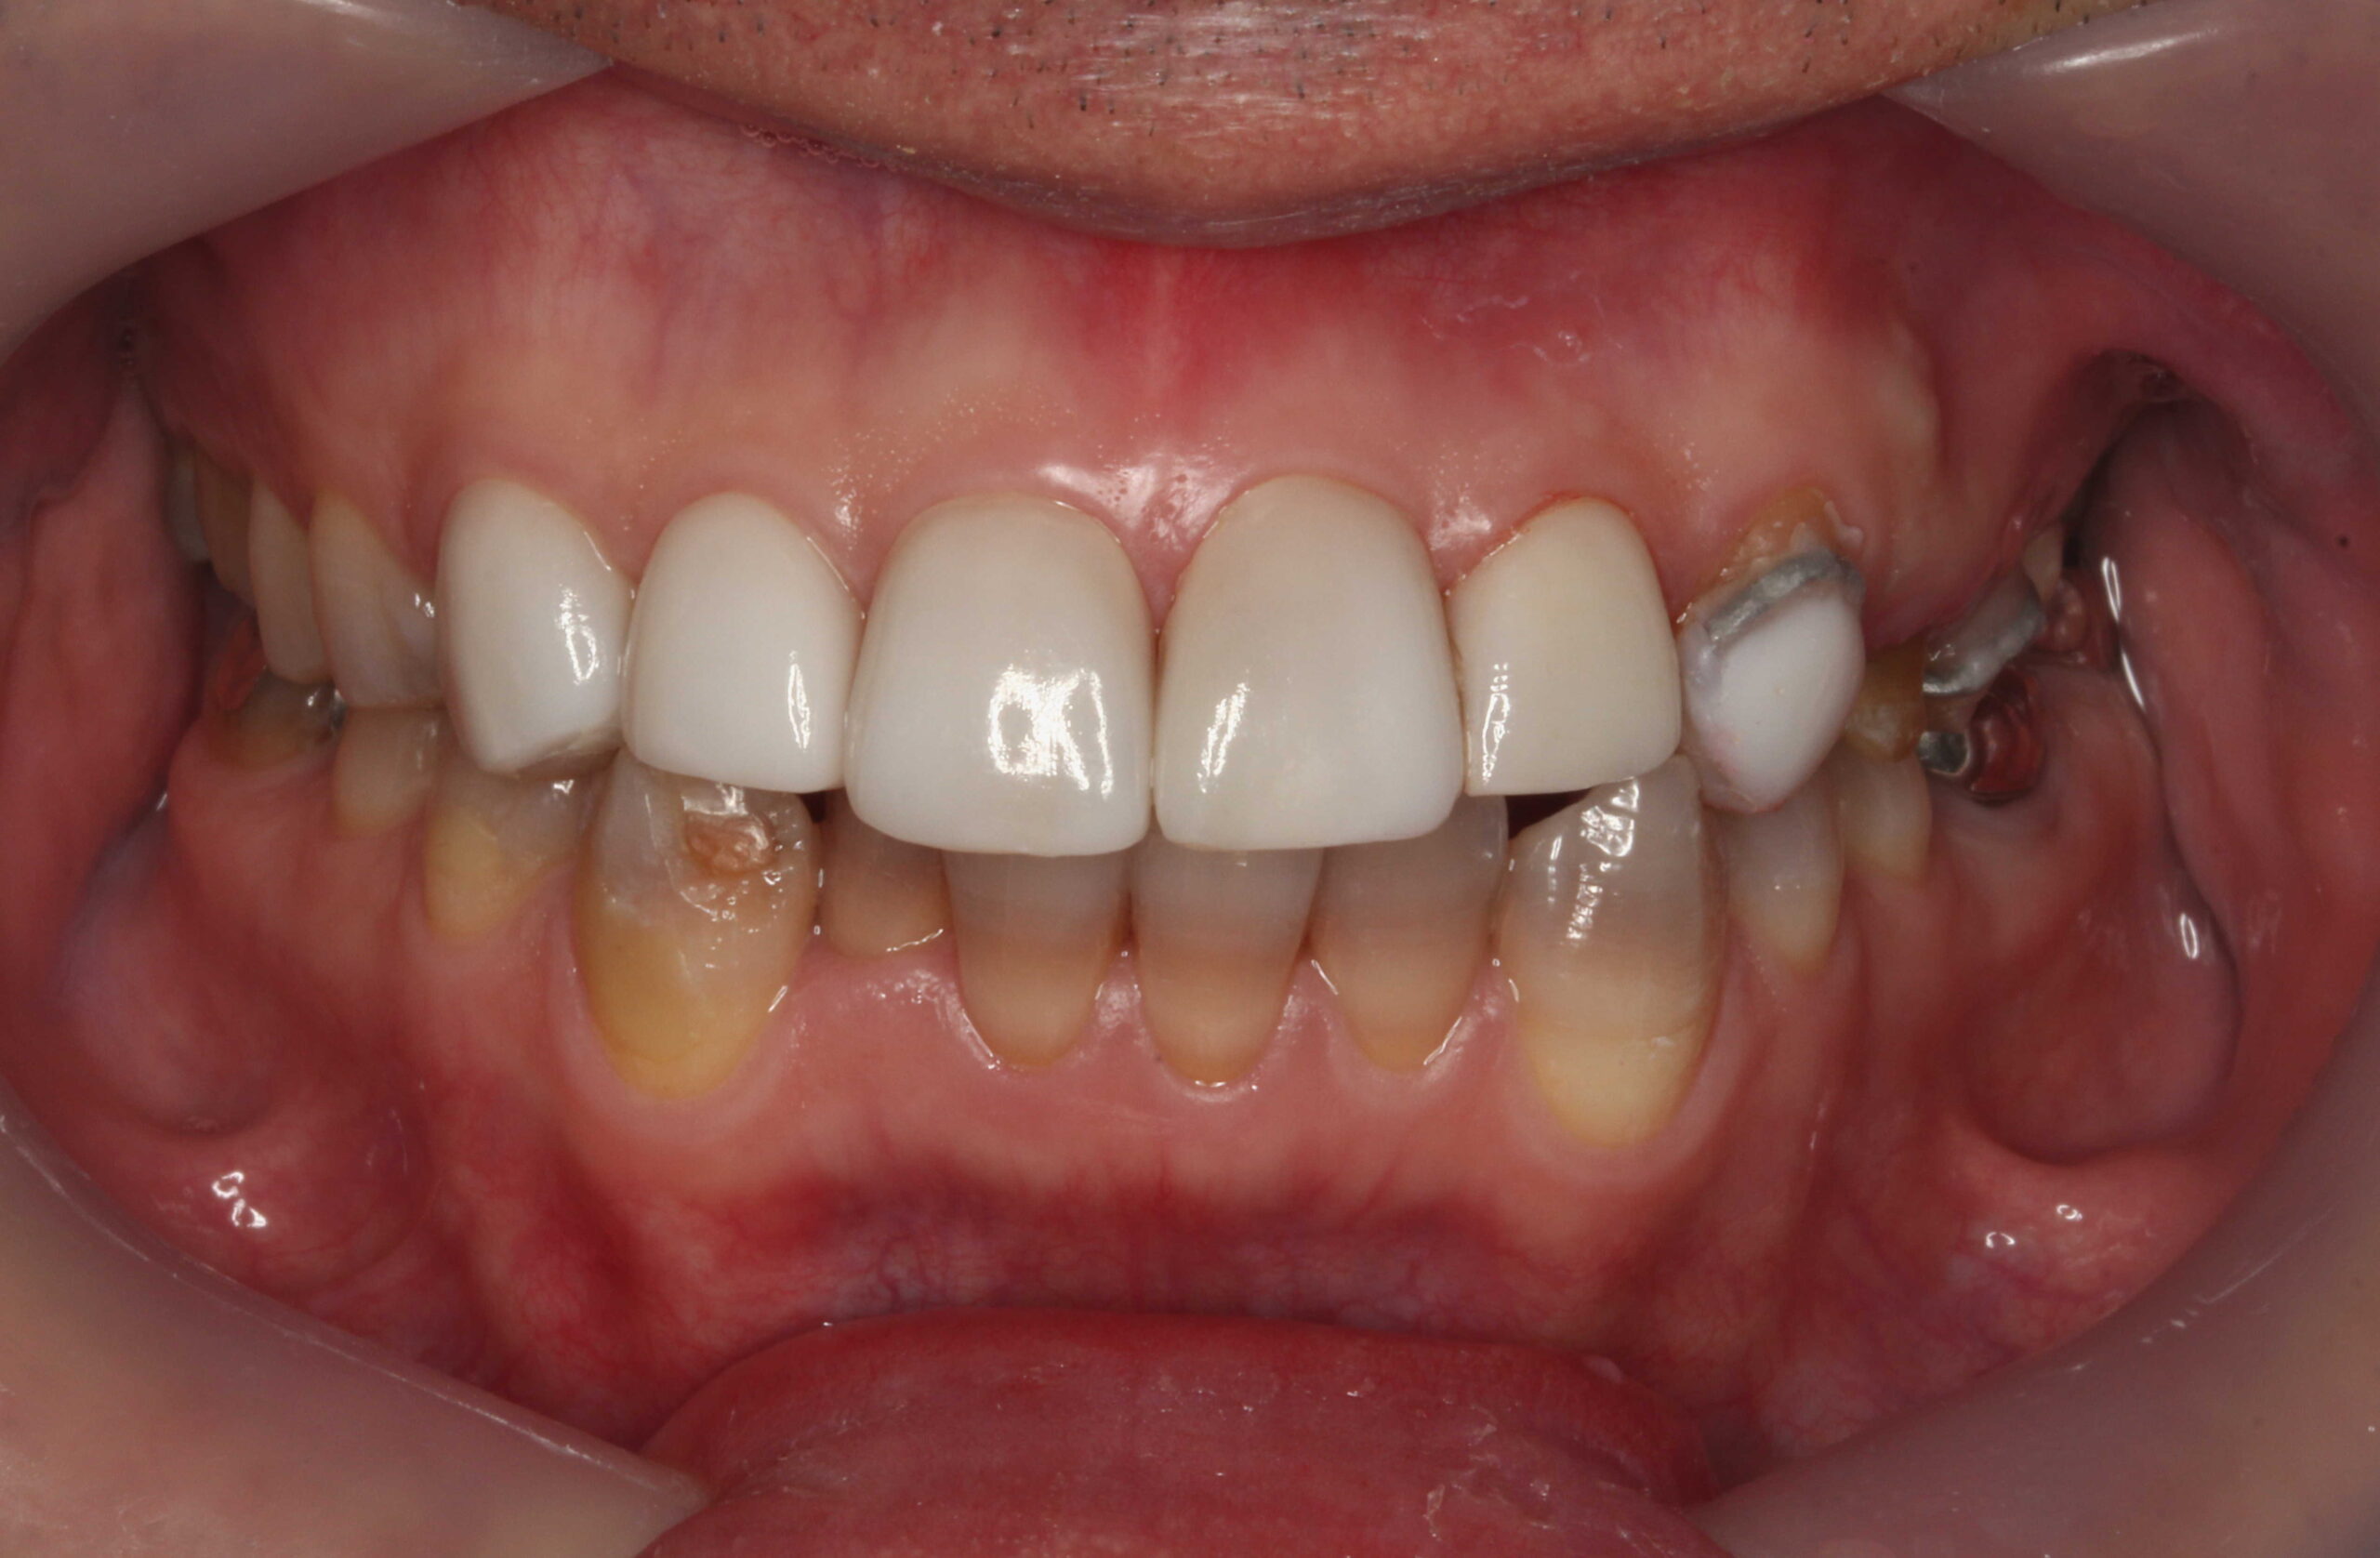

テトラサイクリン歯を他院でセラミッククラウンで被せていた事例

他院にてテトラサイクリン歯を上前歯6本のセラミッククラウンで被せてある症例です。

従来のクラウンの方法では支台になる歯の外周を大きく削ることになってしまいます。

当院でも以前はこのような方法で多くの審美歯科を行っていました。

他院で前歯6本クラウン 当院で右上54、左上45に

削らないラミネートベニア

他院では前歯6本を削ってクラウンで治しています。

患者様は削らない方法で審美的に揃えたいということでご来院されました。

奥の右上54、左上45も削らずに前歯と審美的に揃えたいということで、当院で削らないラミネートベニアで治しました。